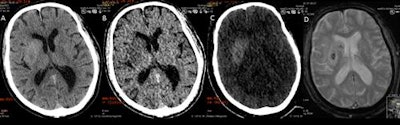

Using dual-energy CT (DECT), characterization of a disruption of the blood-brain barrier and hemorrhage becomes possible using varying attenuation characteristics, which have been activated by two particular energy levels, thereby allowing DECT to differentiate between contrast extravasation and intracranial hemorrhage. Iodine overlay maps can be reconstructed, with a corresponding virtual unenhanced noncontrast image.

DECT can suggest only limited breakdown of the blood-brain barrier, while the MRI gradient echo reveals the true hemorrhage. A: virtual polychromatic CT. B: water-weighted. C: iodine-weighted. D: Gradient-echo sequence of MRI. Image courtesy of Dr. Leonard Yeo.Hyperdensity seen on mixed images and persisting on virtual unenhanced noncontrast images but not on iodine overlay maps is considered a hemorrhage, while a hyperdensity present on mixed images and iodine overlay maps but not on virtual unenhanced noncontrast is considered contrast extravasation.

DECT has an accuracy of 89% in this regard. Routine use of the modality allows for reliable distinction between disruption of the blood-brain barrier and intracranial hemorrhage just after endovascular stroke therapy, so the treating physician can allocate resources such as intensive monitoring and further therapy, according to the authors.